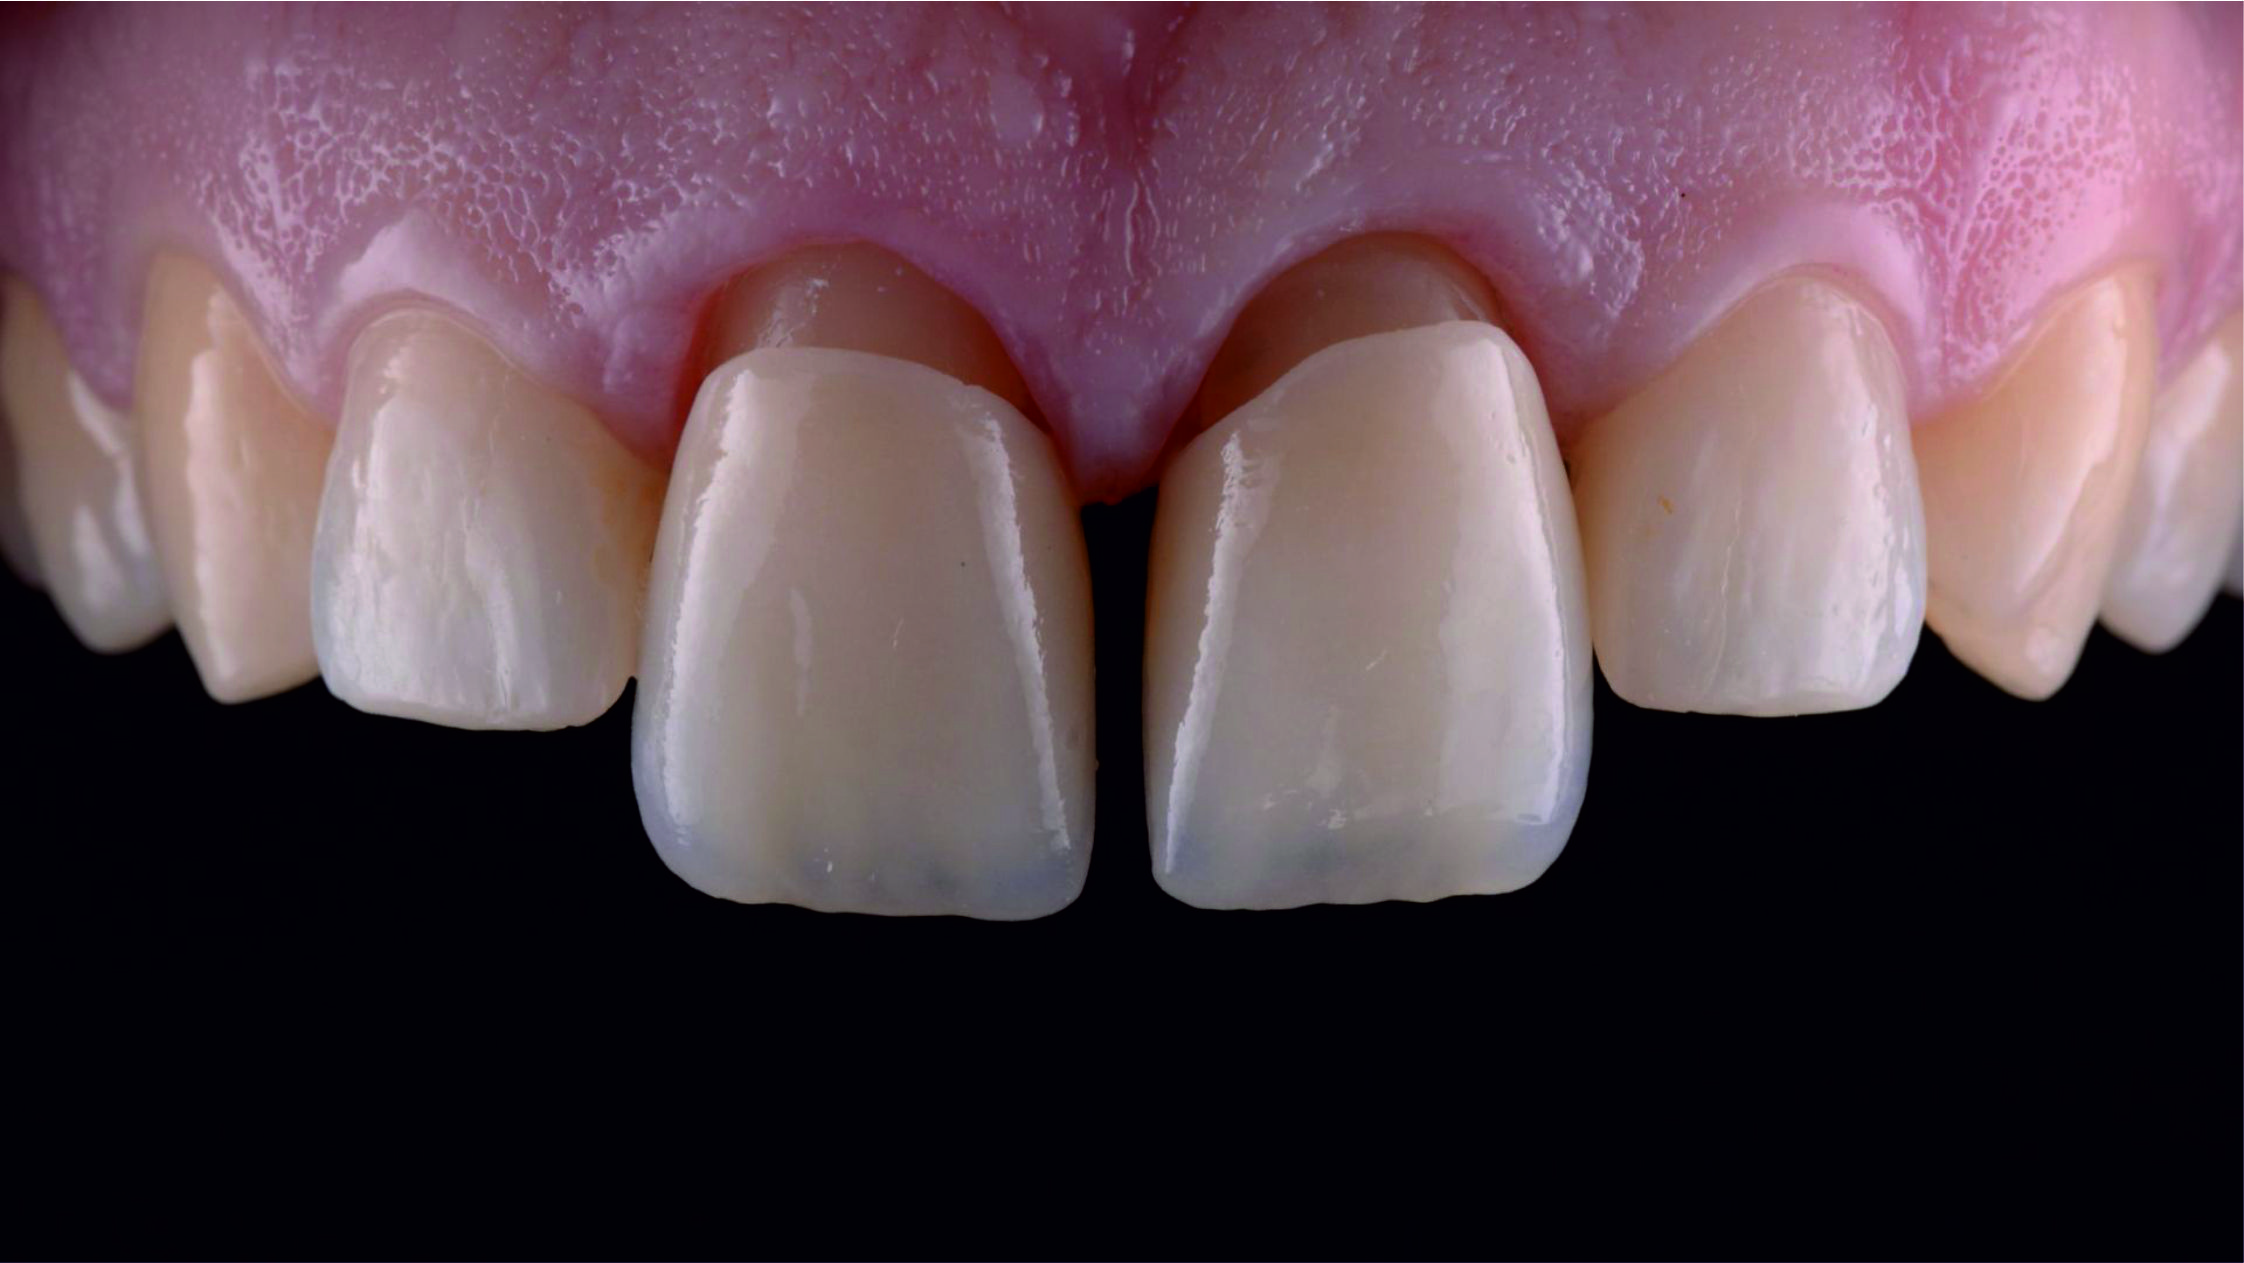

Фото 1. Початкова ситуація: жінка віком приблизно 35 років, із двома металокерамічними коронками, встановленими на верхніх центральних різцях.

Основні скарги: асиметрія центральних різців, запалення й кровоточивість ясен навколо коронок, загальне невдоволення естетикою цієї зони.

Фото 2. Через високо розташовану лінію посмішки можна припустити, що будь-яка вада після лікування обов'язково буде дуже добре помітною.